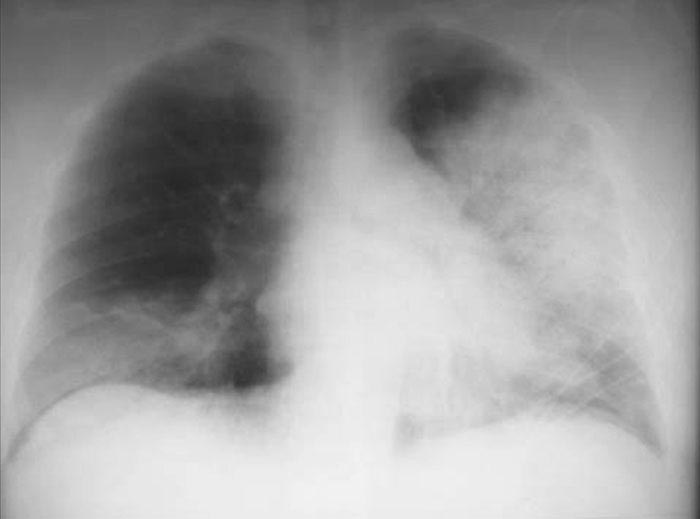

Aspergilosis pulmonar invasiva en influenza severa

En pacientes internados en cuidados intensivos con neumonía por influenza se halló un alto porcentaje de aspergilosis invasiva, aún en ausencia de factores de inmunosupresión. The Lancet Respiratory Medicine, 31 de julio de 2018